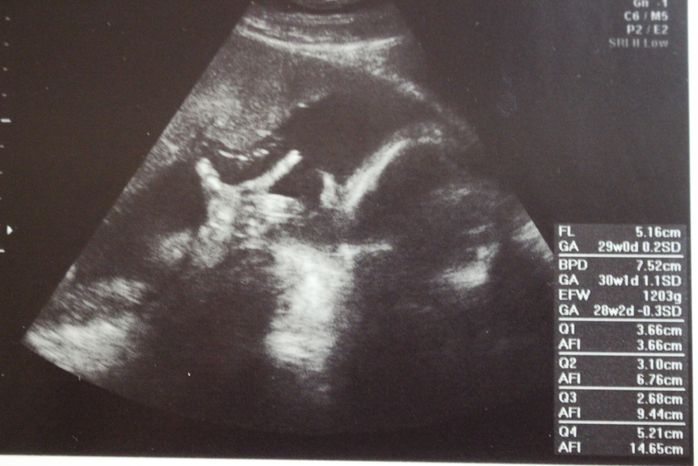

妊娠30週目のエコー写真

口をキュッとつぐむ様子も愛おしい表情。この頃は便秘がひどく、「酸化マグネシウム」を医師に処方してもらいました。この頃は安静にしながらも、週に1回催される母親学級へ車椅子で通い勉強していました。